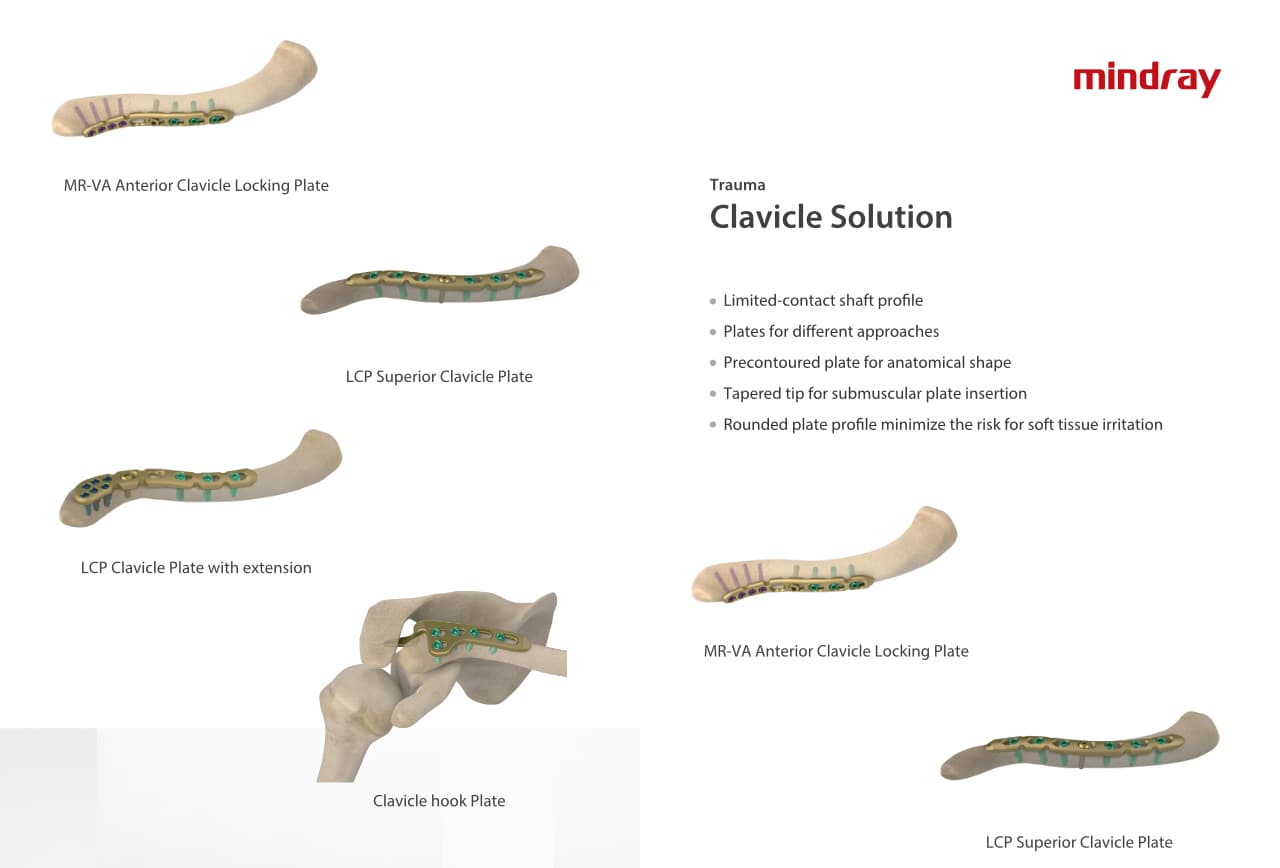

Traumatologie